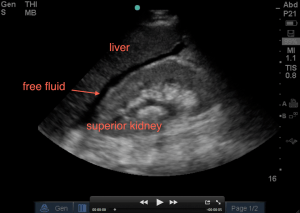

3. Evaluate between the liver and the entire superior pole of the kidney (classic Morrison’s pouch view). Slowly fan anterior to posterior to visualize the entire superior pole of kidney – you should fan to the extent that the kidney goes completely out of view, comes back into view, then goes back out of view.